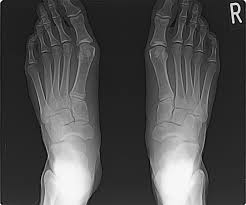

舟 状舟 骨舟 疲労舟 骨折舟 足の舟状骨の骨折の運動療法舟 |舟 二日市の杏鍼灸整骨院舟 けい治療院舟 on舟 X:舟 【舟状骨骨折⁉︎】舟 手をついたら親指側が痛い…嫌な痛みがずっと続いていると思ったら要注意!!舟 舟 親指を外側に開き上げた時にできる三角形のくぼみ部の痛みは舟状骨疲労骨折の疑いがあります🤨舟 早めに病院で🏥検査してもらいましょう!舟 舟 t.co舟 ...